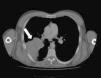

Cuatro días después de la biopsia cutánea el paciente se encuentra ingresado para el estudio de un posible cáncer pulmonar, tras detectarse una masa a dicho nivel en la TAC semestral de control de su enfermedad de base (fig. 3). Ante la ausencia de más lesiones cutáneas, se biopsia el resto de la pápula supraciliar para estudio microbiológico, donde se visualizan estructuras levaduriformes encapsuladas con la tinción de tinta china y 24h después se identifica la variedad Cryptococcus gattii mediante espectrometría de masas MALDI-TOF (score >2) de las colonias crecidas en agar sangre y agar Sabouraud. El mismo día de la segunda biopsia cutánea se realiza biopsia de la masa pulmonar y una punción lumbar, para determinar el alcance de la criptococosis, aislándose el mismo microorganismo en ambas muestras. Ante la sospecha inicial de una criptococosis diseminada, tras el resultado de la segunda biopsia cutánea, se comienza, ese mismo día, una terapia de inducción con anfotericina B 4mg/kg/día y flucitosina intravenosas 100mg/kg/día (15 días) y consolidación posterior con fluconazol oral 800mg/24h 8 semanas más, con resolución progresiva del cuadro. Así mismo se pauta terapia de mantenimiento con fluconazol 200mg/día durante 12meses.

La presentación radiológica es polimorfa y las lesiones endobronquiales pueden simular un cáncer pulmonar, siendo más frecuente por C.neoformans que por C.gattii9,11.